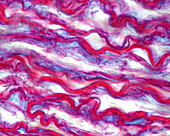

13613450 - Elastic lamellae in aorta, light micrograph

13613436 - Elastic lamellae in aorta, light micrograph

13613447 - Elastic lamellae in aorta, light micrograph

13613449 - Elastic lamellae in aorta, light micrograph

13613433 - Elastic lamellae in human aorta, light micrograph